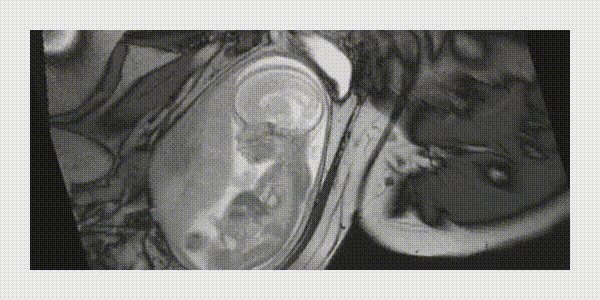

A avaliação do sistema nervoso central fetal (cérebro e medula espinhal) durante o período gestacional é muito importante e complexo. O desenvolvimento do sistema nervoso central do feto é dinâmico, uma longo e extraordinária jornada até a sua completa formação. Avaliar este desenvolvimento durante o período gestacional é desafiador e realizado pelos médicos especialistas em medicina fetal através dos exames de ultrassonografia morfológica do feto. Apesar do constante avanço e aprimoramento dos exames de ultrassom, tanto tecnológicos quanto dos profissionais dedicados exclusivamente a medicina fetal, a ressonância magnética é um método auxiliar muito importante em algumas situações durante este acompanhamento. O desenvolvimento tecnológico exponencial do exame de ressonância magnética permite a realização de exames seguro para a mãe e para o feto, de forma rápida e com um minucioso detalhamento e visualização de todas as estruturas do cérebro do feto.

- O exame é realizado em um aparelho de ressonância magnética, sem nenhum risco para a mãe e para o feto.

- Não há utilização de radiação e nem de contraste neste exame.

- Em média o exame dura em torno de 10 a 20 minutos.

- O posicionamento no aparelho é realizado de forma a proporcionar o maior conforto possível para a gestante e para o feto.